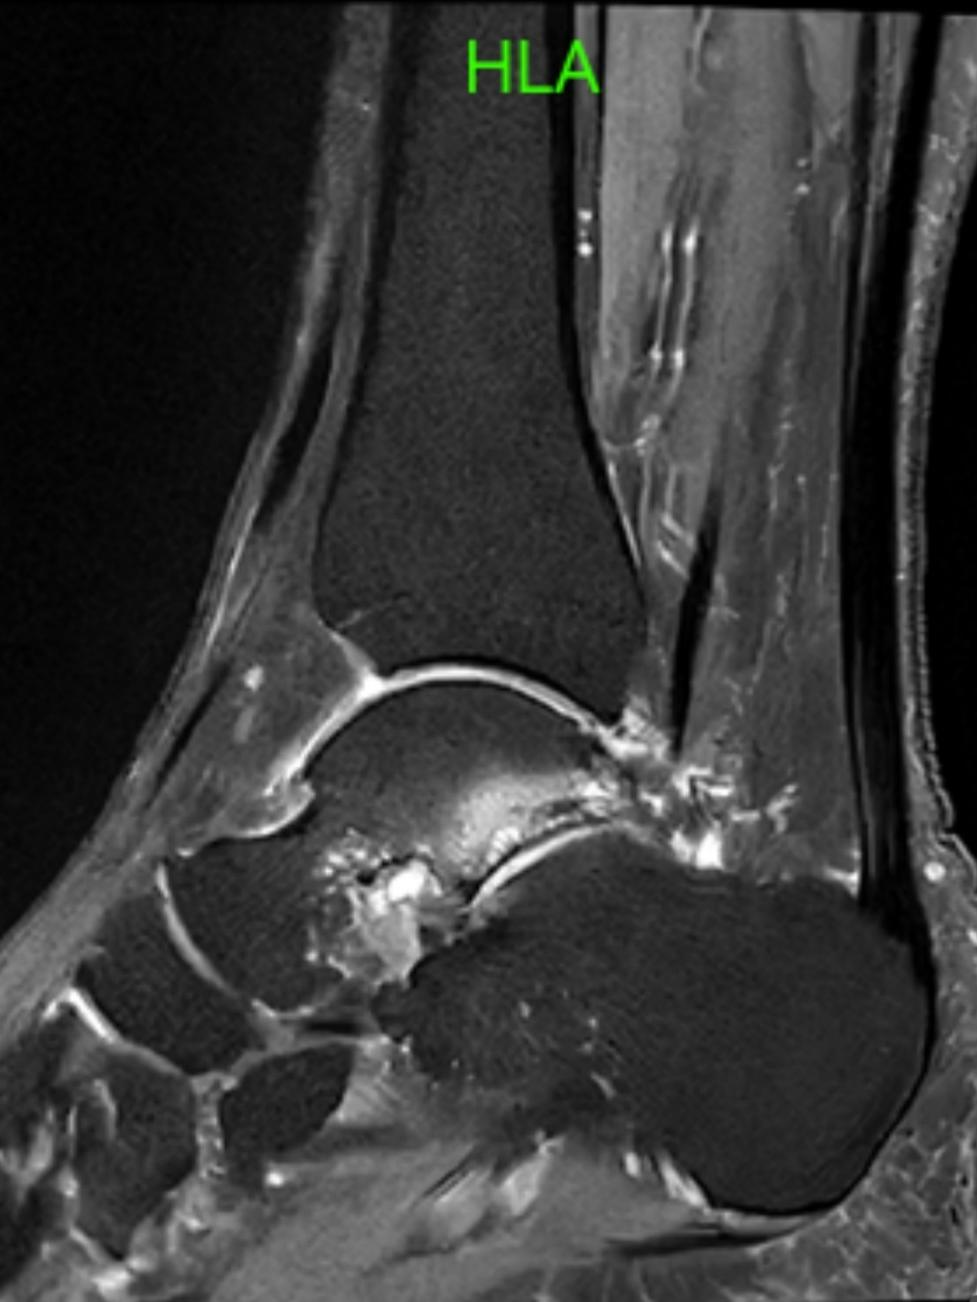

术前踝关节矢状位MRI提示在距骨后突后方可见异常骨结构(三角骨)并伴有骨髓水肿,周围伴随滑膜增生、软组织水肿(高信号影)